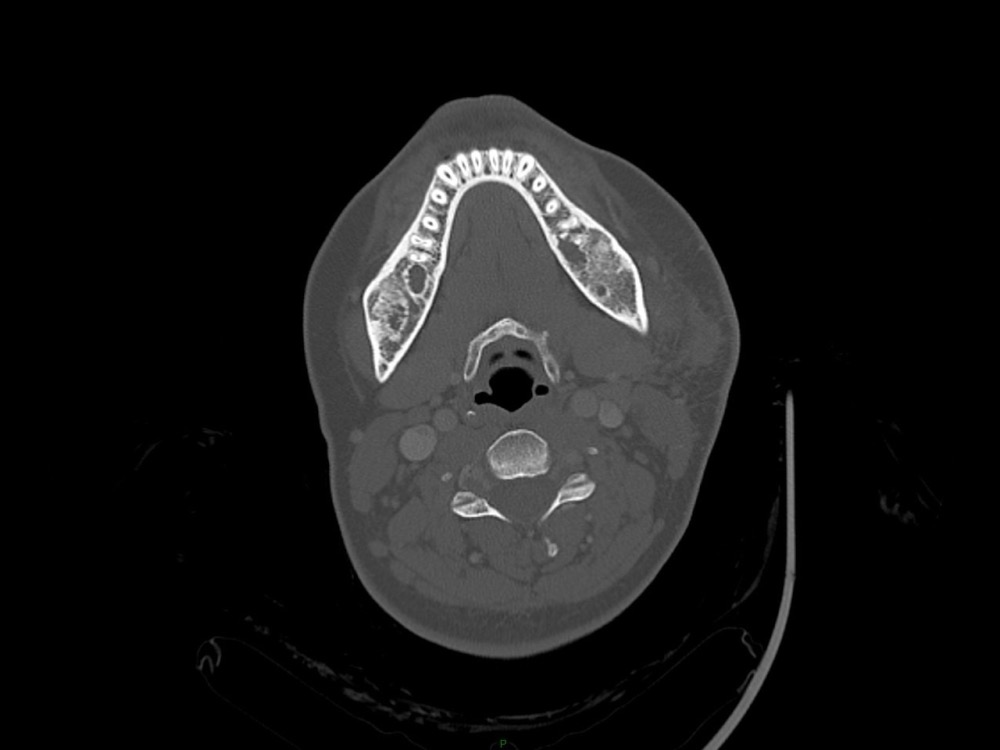

Arsovic / Perrot / Miquel 18/05/2022